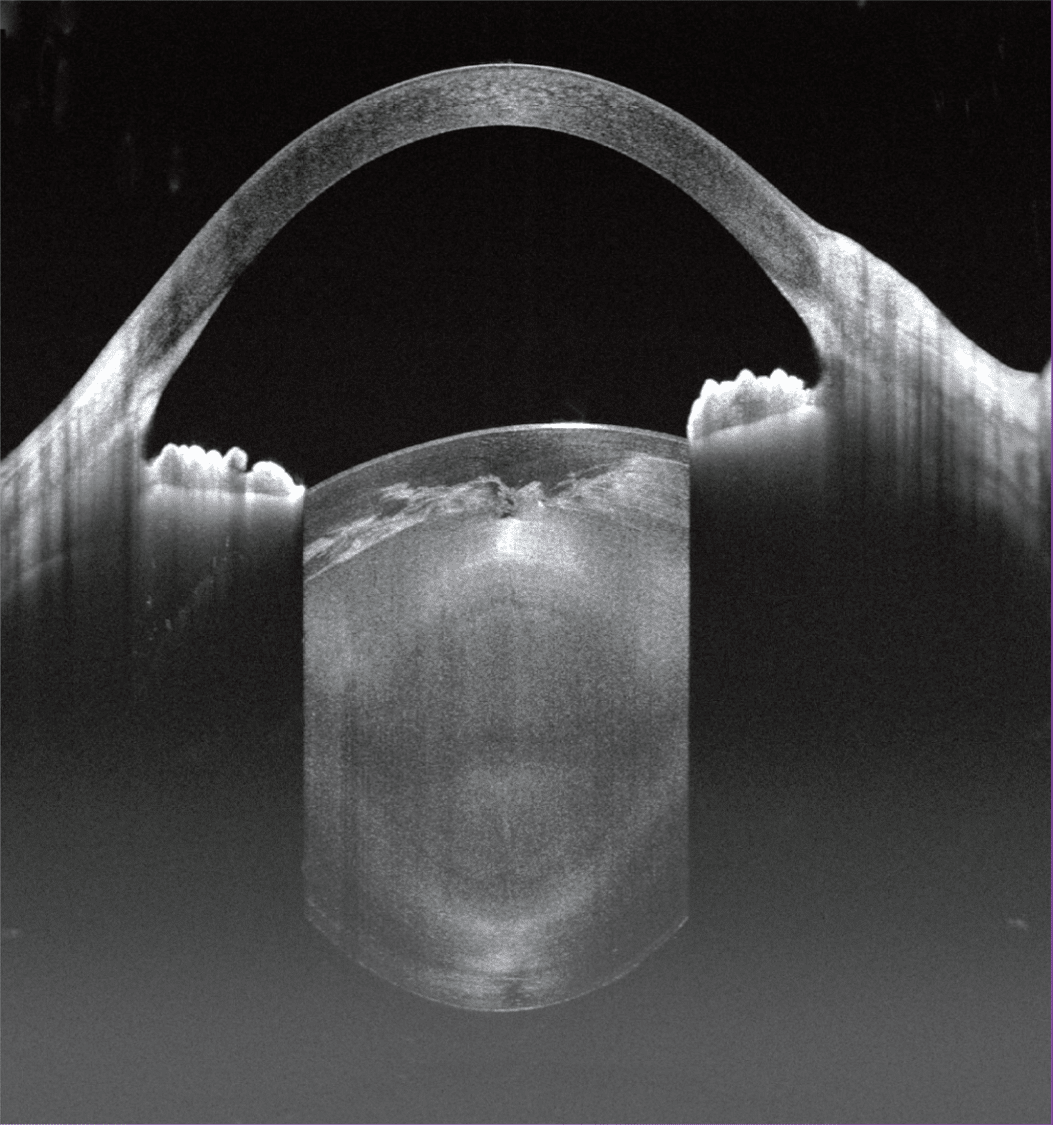

- HD Anterior Scan with Anterior OCTA

- 15mm Scan depth anterior